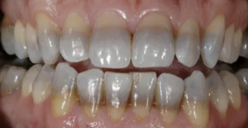

The teeth in the following image are stained due to:

tetracycline